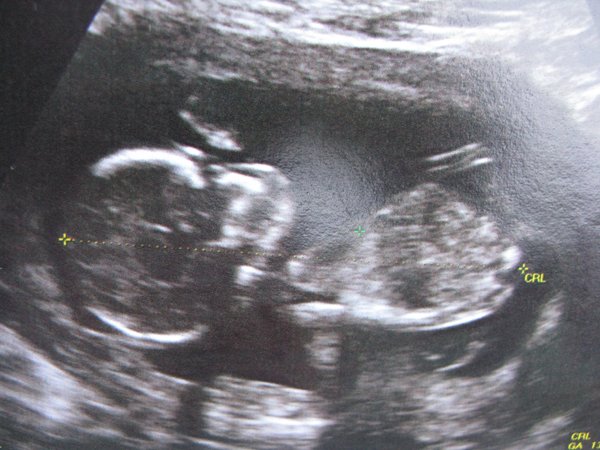

Én is itt vagyok, de nagyon elkeserdve. Annyira depis voltam az integrált óta, hogy nem is volt lelkierőm írni. A babával minden okés, 80 % hogy kislány (amit szeretnénk is), tarkóredő 1,4, szóval minden tökéletes lenne,